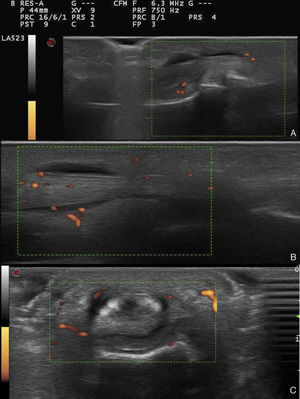

Ultrasound images of the 4th finger of the patient's right hand. (A) Long-axis view of middle-distal phalanges, with grade 1 power Doppler signal. (B) Long-axis view of proximal phalanx-metacarpus, with grade 2 power Doppler signal. (C) Cross-sectional view of proximal phalanx-metacarpus, with grade 2 power Doppler signal.

We report the case of a 37-year-old man with PsA that began in 2003 with skin involvement, and eventually affected his joints. He started taking methotrexate in 2014, and is currently in clinical remission. At his last check-up, his cutaneous condition had worsened and he complained of apparently mechanical pain in the fourth finger of his right hand. Clinical examination found nothing of interest, whereas ultrasound revealed acute tenosynovitis of the flexor tendon in that finger, affecting the entire volar portion (Fig. 1). The clinical signs remitted after ultrasound-guided corticosteroid injection.